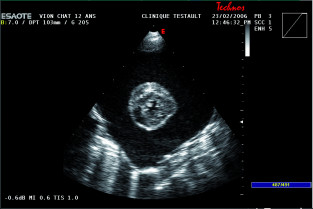

La section Poitou-Charente vous propose une soirée de formation sur les urgences cardio-respiratoires. A l'issue de cette formation, le particpant devra être capable de reconnaître l'urgence, mettre en œuvre les examens complémentaires adapter et de mettre en place le traitement.

- Reconnaître l'urgence

- Mettre en œuvre les examens complémentaires adaptés

- Mettre en place et adapter le traitement

- Établir le pronostic